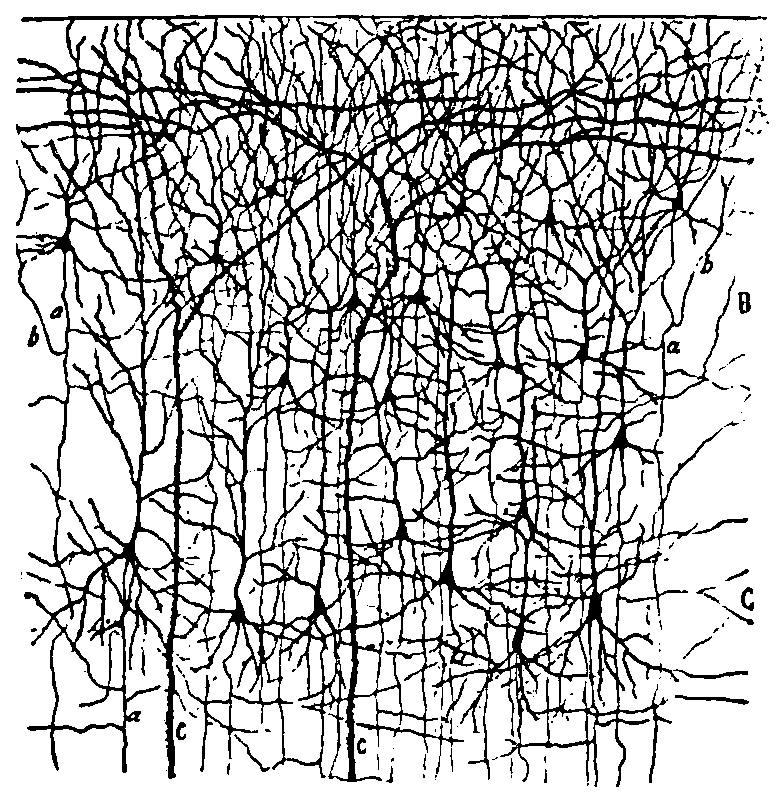

| 3. | Small and medium-sized pyramidal cells of the visual cortex of a child twenty days old | 110 |